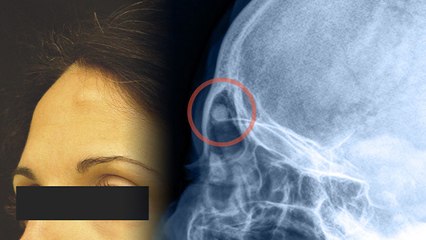

पलक में गांठ या दानें, दर्द महसूस हो तो इसे हल्के में ना लें क्योंकि यह इंफेक्शन का संकेत हो सकता है। मेबोमियन या ऑयल ग्लैंड में ब्लॉकेज के कारण पलकों की ग्रंथि में गांठ बन जाती है, जिसके कारण काफी दर्द होता है। हालांकि कई बार यह बिना इलाज कुछ दिनों में ठीक हो जाती हैं लेकिन इसे हल्के में लेना खतरनाक हो सकता है क्योंकि आमतौर पर यह बिलनी होने के बाद विकसित होती है। वहीं पलकों पर बनी गांठ Eye Cancer का संकेत भी हो सकती है। br br If you feel a lump or rash in the eyelid, pain, then do not take it lightly as it can be a sign of infection. A blockage in the meibomian or oil gland leads to the formation of a lump in the gland of the eyelids, due to which there is a lot of pain. Although sometimes it gets better in a few days without treatment, it can be dangerous to take it lightly as it usually develops after a twitch. At the same time, a lump formed on the eyelids can also be a sign of Eye Cancer.